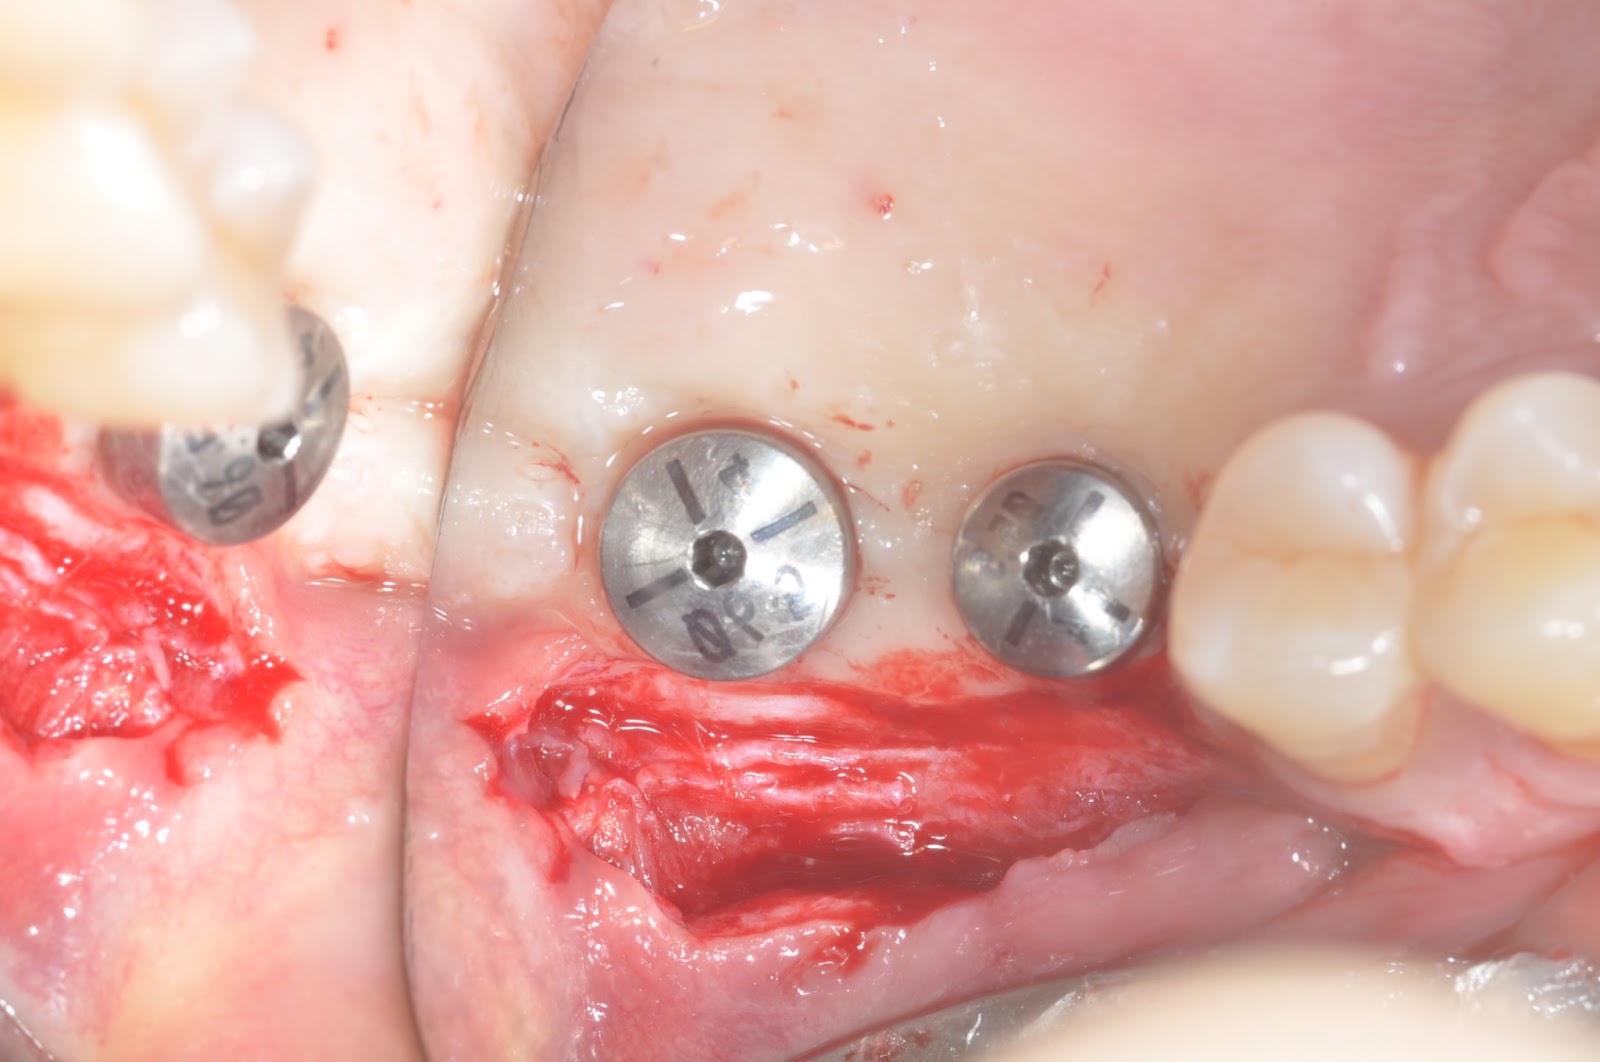

VISTA for single upper anterior tooth + GBR

Osseous defects

Bio-Oss(L) + Bio-Glide

Suturings

4 wks’ healing

6 mo healing